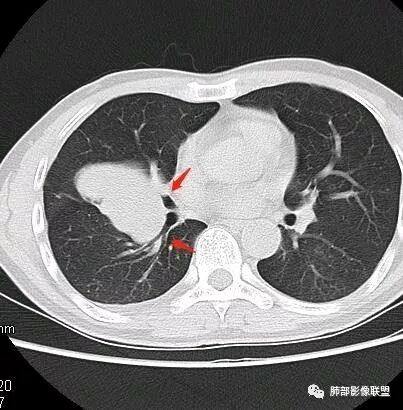

南边:深分叶、大肿块

南边:主体在下叶前基底段

南边:边缘膨隆

南边:中叶、下叶背段支气管推移

南边:中叶支气管腔内似有粘液栓,外侧段有炎性病变

南边:有老师问为啥考虑中叶支气管受压?不是支气管来源的?

1、主体病灶在下叶

2、支气管腔还在,有移位

但是现在的片显示,其主体在下叶,中叶支气管壁由下朝上有推移

南边:下叶的支气管受压后移、变形

南边:病灶边界清,提示侵袭性弱,膨胀生长为主;这时候我们提示病灶不应该是支气管关系密切,提示间叶来源或胸膜来源

深分叶,警惕恶性